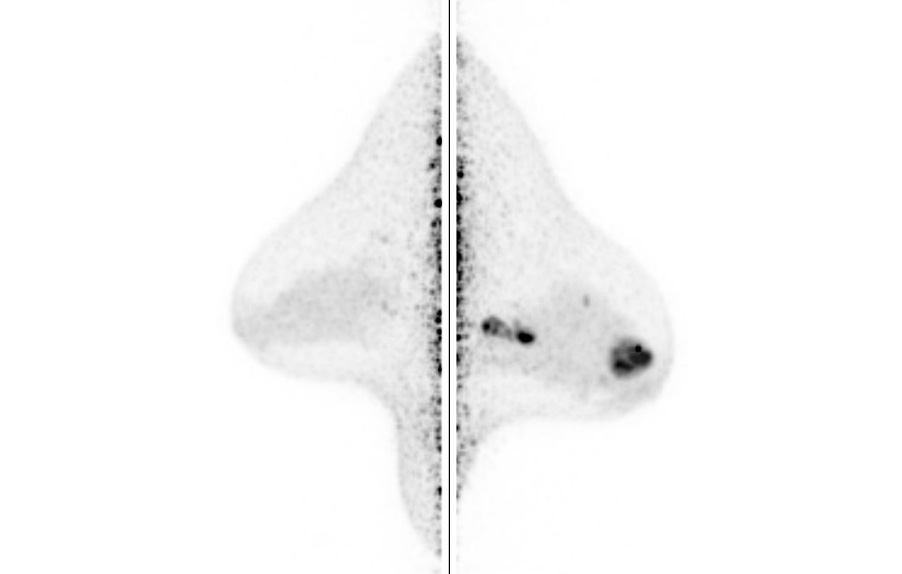

Breast / Case2 : FDG

CC-MIP

ML-MIP

Courtesy : Kindai University Hospital

- Imaging protocol

- Injected dose: 2.88 MBq/kg, 18F-FDG

- Scan time: 5 minutes